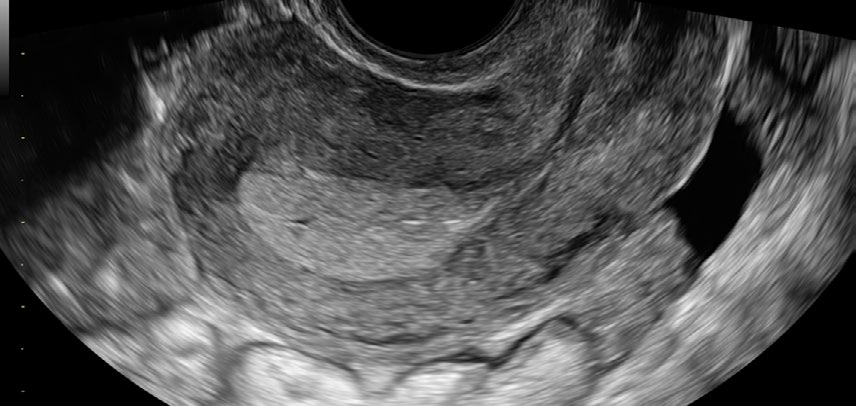

El Voluson Signature 18 se basa en un nuevo motor de imágenes: la arquitectura Voluson Unity, que ofrece velocidades de procesamiento y velocidades de fotogramas más rápidas que nuestros sistemas Signature anteriores. Este hardware y software son la base del sistema y sientan las bases para las capacidades actuales y futuras. Experimente ahora un nuevo nivel de profundidad y claridad.

Con solo tocar un botón, reduzca el ruido y aumente la penetración incluso en los pacientes más difíciles para obtener imágenes limpias, sólidas y homogéneas.

Reduce las sombras en las imágenes que pueden oscurecer las estructuras adyacentes ayudando a restaurar la información y los bordes del tejido.